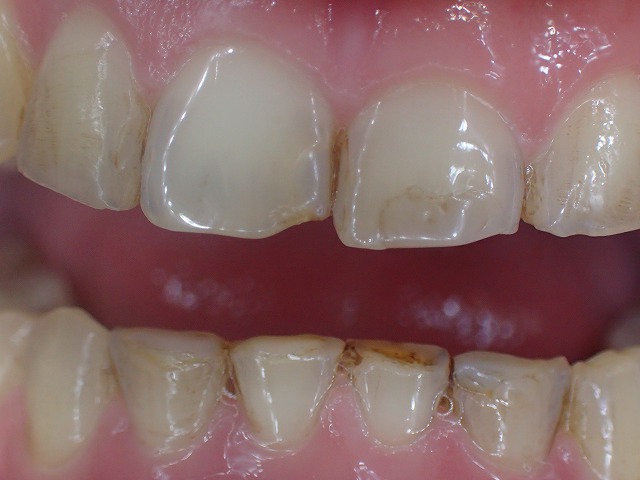

咬み合わせ診査

かなり深い過蓋咬合です。(咬み合わせが深い)

●過蓋咬合

●重度の歯ぎしり

●左右不対象

●前歯の摩耗部分にレジン充填

かなりの歯ぎしりで、前歯がバリバリに削れています。

左右不対象が気がかりです。

上顎前歯

激しく摩耗している

顎の動きで左右非対称に摩耗しているの

過蓋咬合なので上顎前歯の内側の摩耗が激しい

歯並びが左右非対称